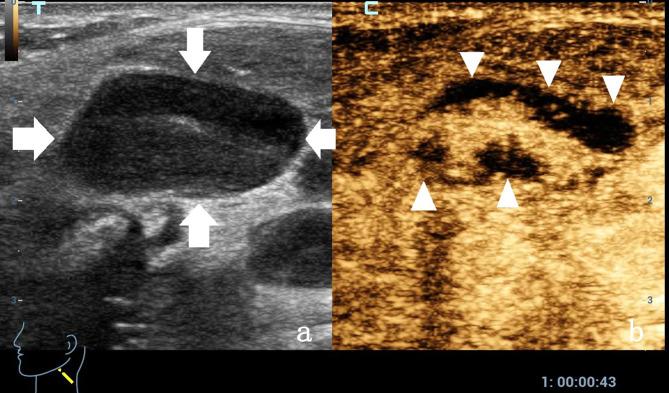

To investigate the value of contrast-enhanced ultrasound (CEUS) assisted core needle biopsy (CNB) in the diagnosis of cervical lymph node tuberculosis (LN TB) and improve the positive rate of cervical LN TB.

We retrospectively analyzed 730 samples obtained from July 2010 to January 2025 from patients treated with effective antituberculosis therapy and with microbiologically confirmed and surgical pathologically proven cervical lymph node enlargement who had undergone CEUS- CNB at our hospital. All patients were divided into two groups according to the historical control method. The CEUS group (2017-2025) underwent CEUS- CNB (485 cases), whereas the US group (2010-2018) underwent US-guided CNB (245 cases). The positive rates of pathological diagnosis and Xpert Mycobacterium tuberculosis complex (MTBC) and resistance to rifampin (RIF) (MTB/RIF) assay diagnoses were compared between the groups.

The specimens' integrity was significantly higher after CNB in the CEUS group than in the US group (CEUS group: 72.30%; US group: 45.49%), and visual satisfaction of sampling in the CEUS group was higher (χ2: 47.651, P < 0.001). Histopathological examination sensitivity, specificity, positive predictive value, and negative predictive value were higher in the CEUS group than in the US group. The sensitivity of the Xpert MTB/RIF assay was significantly higher in the CEUS group than in the US group.

The study results support the clinical use of CEUS for improving the diagnostic performance and positive rate for cervical LN TB.